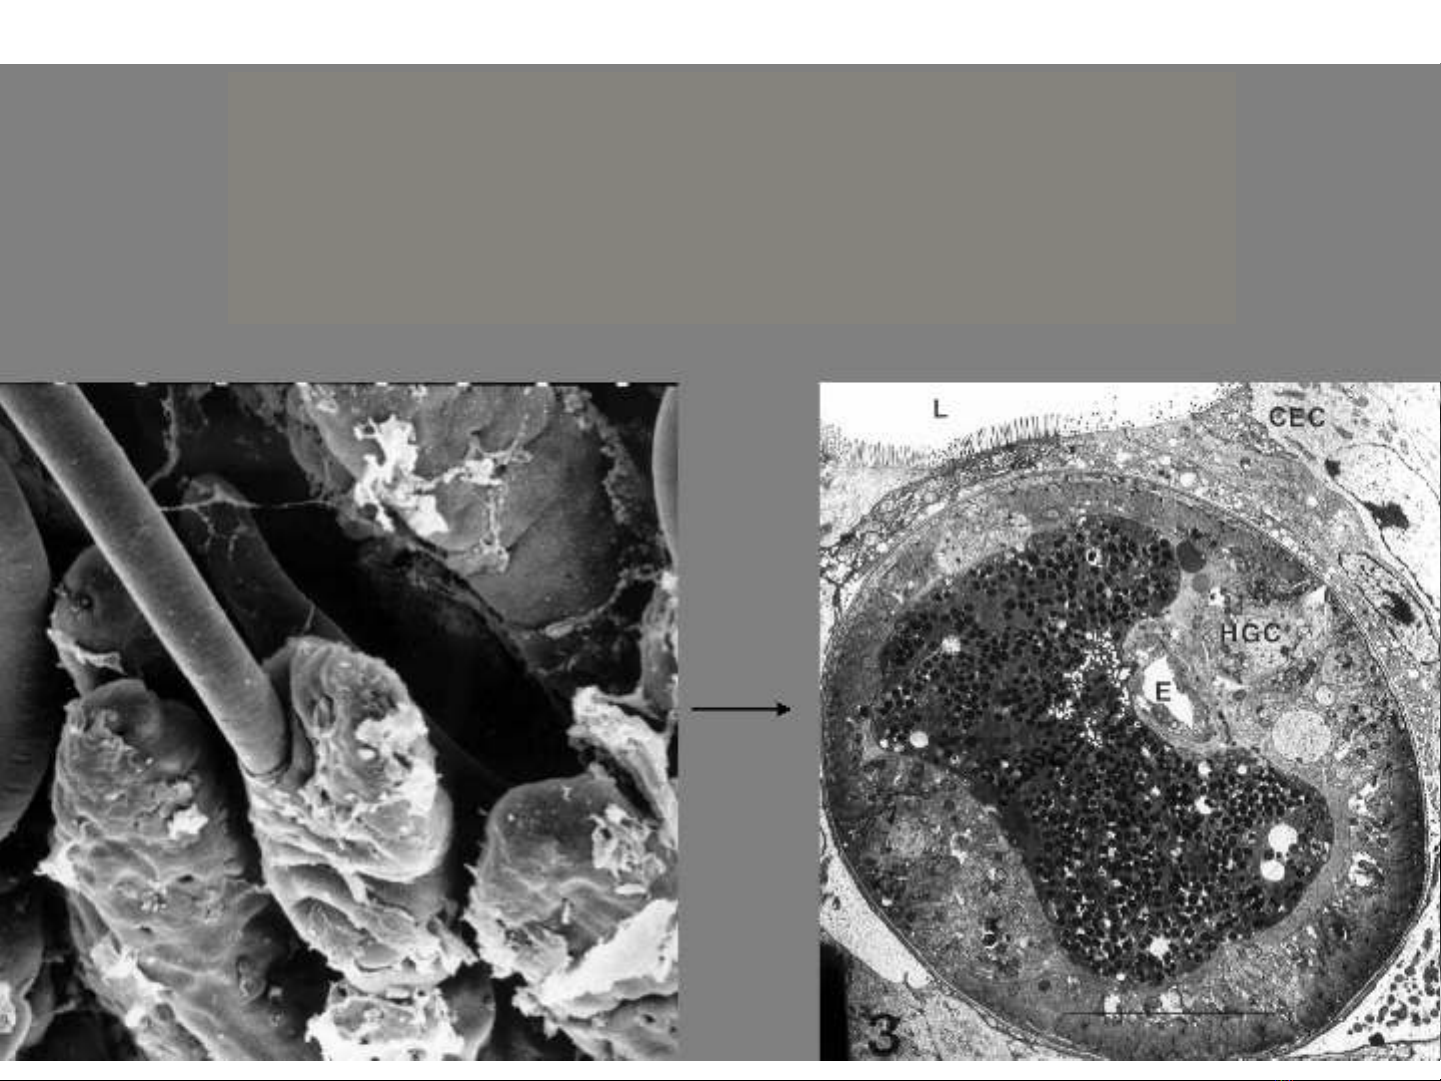

u trùngẤ

Trong s i cợ ơ

Giun bao r t nh , khi vào ru t non nó chui raấ ỏ ộ

kh i kén và chui qua l p t bào thành ru tỏ ớ ế ộ